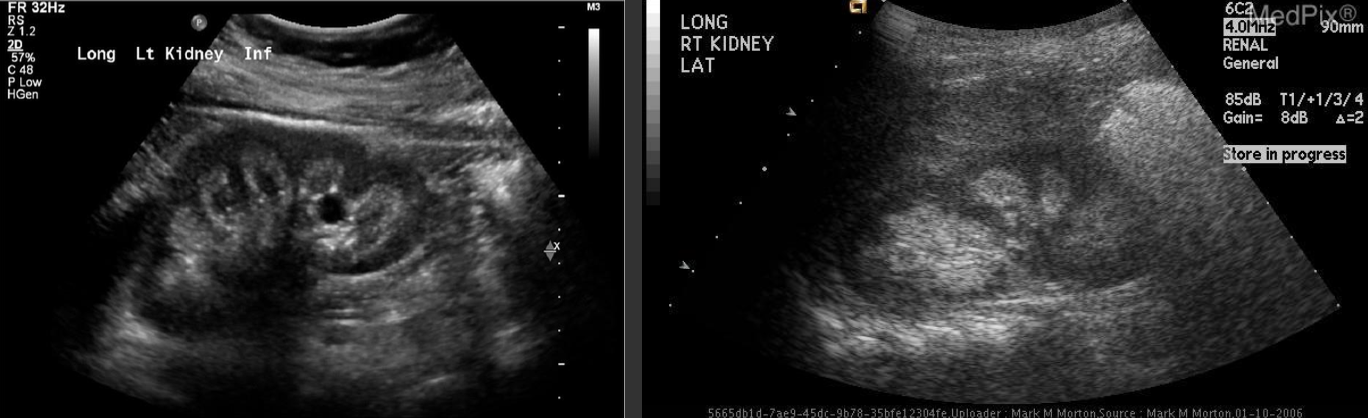

Hydronephrosis → dilation of renal collecting system from mechanical obstruction or functional dysfunction (calculi, mass, trauma, pregnancy)

2D US: grade 1 (mild) → pelviectasis, cortex preserved, grade 2 (mild to moderate) → expands into major calyces, cortex preserved, grade 3 (moderate) → expand all calyces, entire pelvis dilated, cortex preserved, grade 4 (severe) → cortical thinning, AKI to CKD, creatinine >1.2

color doppler: avascular

DDX: parapelvic cysts